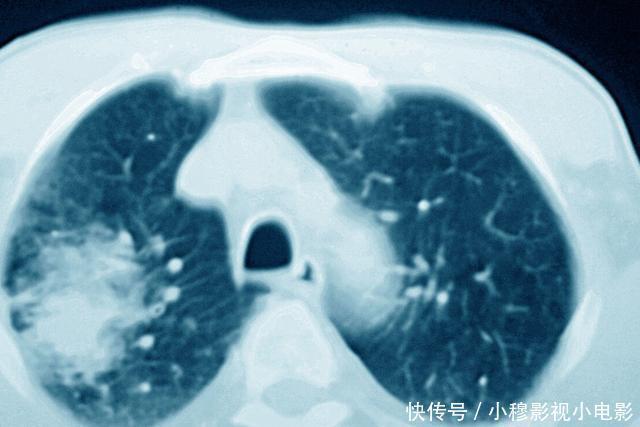

文章插图

作用三:对某些癌症,可以评估治疗效果。

对于有的癌症,CT还能够起到评估治疗效果的作用;有的癌症患者,在发现的时候已经没有了手术治疗的机会;也有的癌症,本身就不适合手术治疗,这个时候可能就需要放化疗等其他的治疗方法来治疗癌症。那么对于这些治疗方法,往往评估疗效非常重要的办法就是进行CT检查。

比如淋巴瘤,大部分淋巴瘤患者都是没有办法进行手术切除的,主要的治疗方法是化疗和放疗。而在进行化疗之后,医生需要判断化疗的效果,这个时候往往就需要结合CT检查,通过CT检查,了解病灶有没有缩小、减少,如果病灶出现了缩小、减少,那么说明治疗有效果,而如果复查病灶没有明显的变化,那么则说明化疗效果不佳,可能需要调整治疗方案。